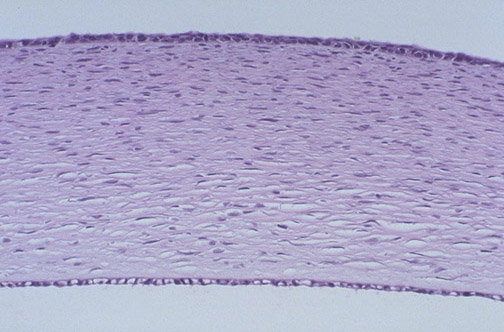

| The structures of a normal fetal cornea are seen starting anteriorly, including the stratified squamous epithelium, the Bowman's membrane, the substantia propria or stroma which is mainly type 1 collagen, the Descemet's membrane, and the Descemet's endothelium. |